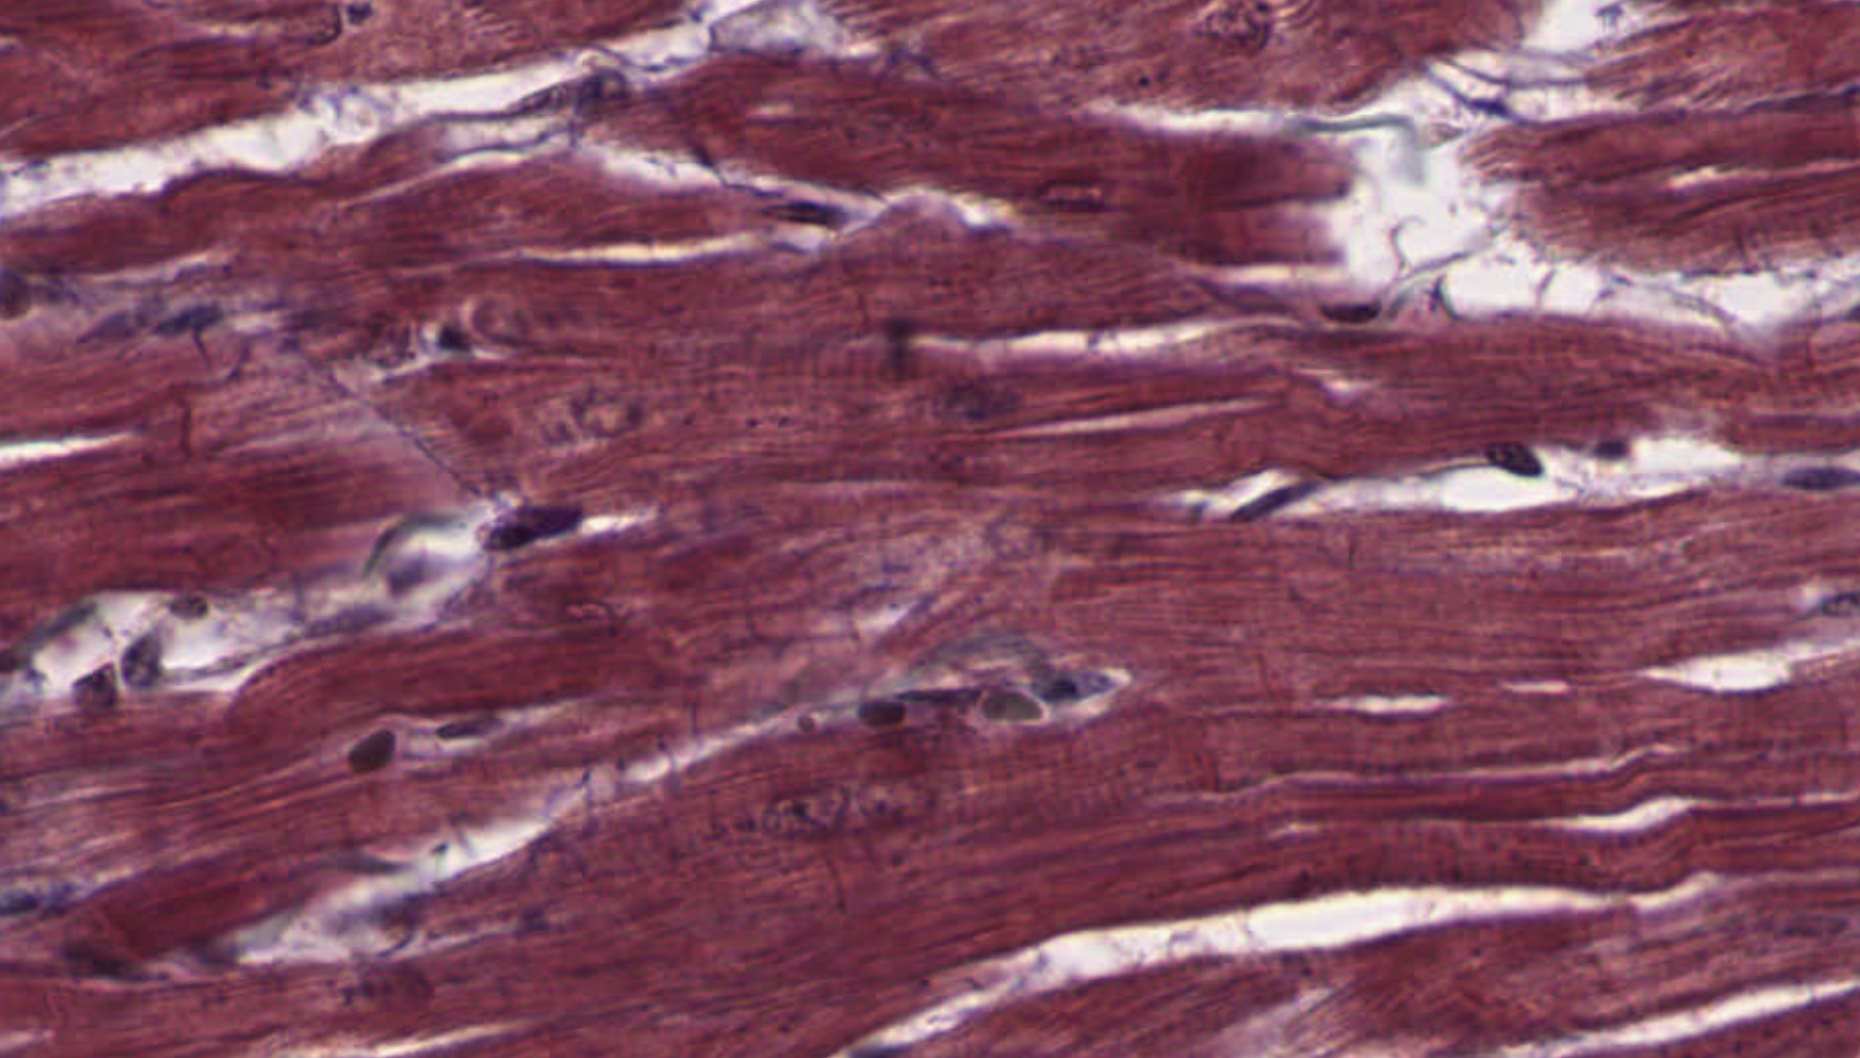

Cardiac Muscle Detail β€” Slide 098 Β· Masson's Trichrome Β· Right Heart WallNow zoom in on the cardiomyocytes themselves. These are the red/pink branching fibers. Look for the central nucleus in each cell, the faint striations, and the intercalated discs β€” the dark transverse lines where two cardiomyocytes meet end-to-end.

Cardiac muscle right heart wall Masson's Trichrome

Cardiac muscle β€” right heart wall Β· Masson's Trichrome Β· Slide 098 Β· bettybroadbent.com

Click each numbered chip to reveal the labeled structure

Clinical Connection β€” Myocardial Infarction & Fibrosis

Cardiac muscle cannot regenerate after death. Following an MI, necrotic cardiomyocytes are replaced by scar tissue β€” dense irregular CT. On Masson's, this appears as an expanding blue patch where red muscle used to be. Cardiologists call this replacement fibrosis. You now know exactly what that scar looks like. A large enough scar reduces contractile force and can cause conduction problems β€” the scar is electrically silent, and action potentials must route around it.